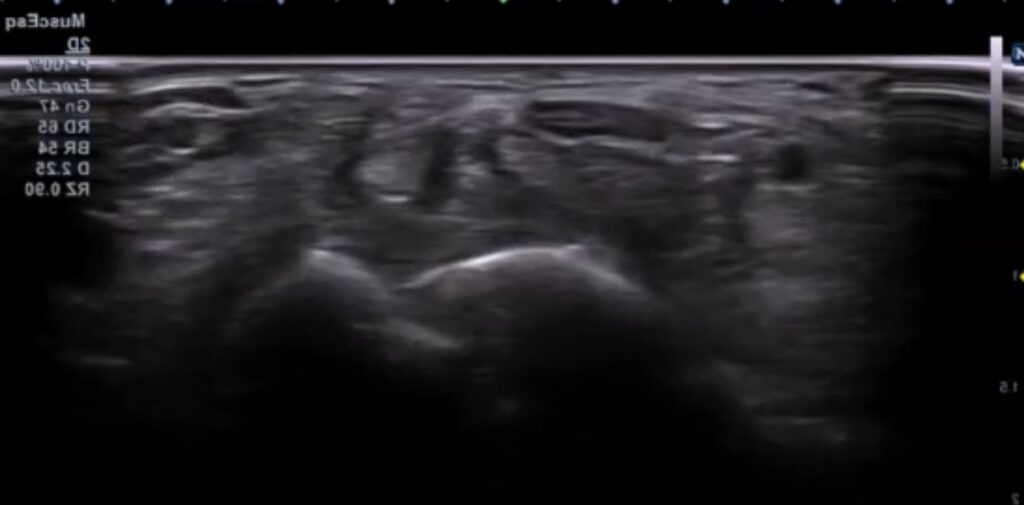

Esta imagen de un corte transversal de la muñeca, nos da un esquema muy claro sobre las estructuras que encontraremos.

De forma superficial al ligamento transverso del carpo, encontraremos el flexor cubital del carpo, el palmar largo (estos dos sin vaina sinovial) y el flexor radial del carpo. El palmar largo es un músculo inconstante, por lo que no siempre estará presente.

Si nos vamos a una capa más profunda, en lo que conocemos como el túnel del carpo, encontraremos una primera hilera de tendones que corresponden al músculo flexor superficial de los dedos.

La tercera capa en profundidad incluirá los cuatro tendones del flexor profundo de los dedos y el flexor largo del pulgar.

No hay que perder de vista que el nervio mediano se encuentra inmediatamente superior a los tendones de la musculatura flexora.

A la hora de explorar la región, realizaremos un corte transversal buscando el hueso pisiforme como nuestra referencia anatómica.

El nervio mediano discurre superficialmente a los tendones flexores superficial y profundo de los dedos. Tendrá una forma ovalada y en una interfase superior, veremos una película hiperecogénica que corresponde al ligamento transverso del carpo.